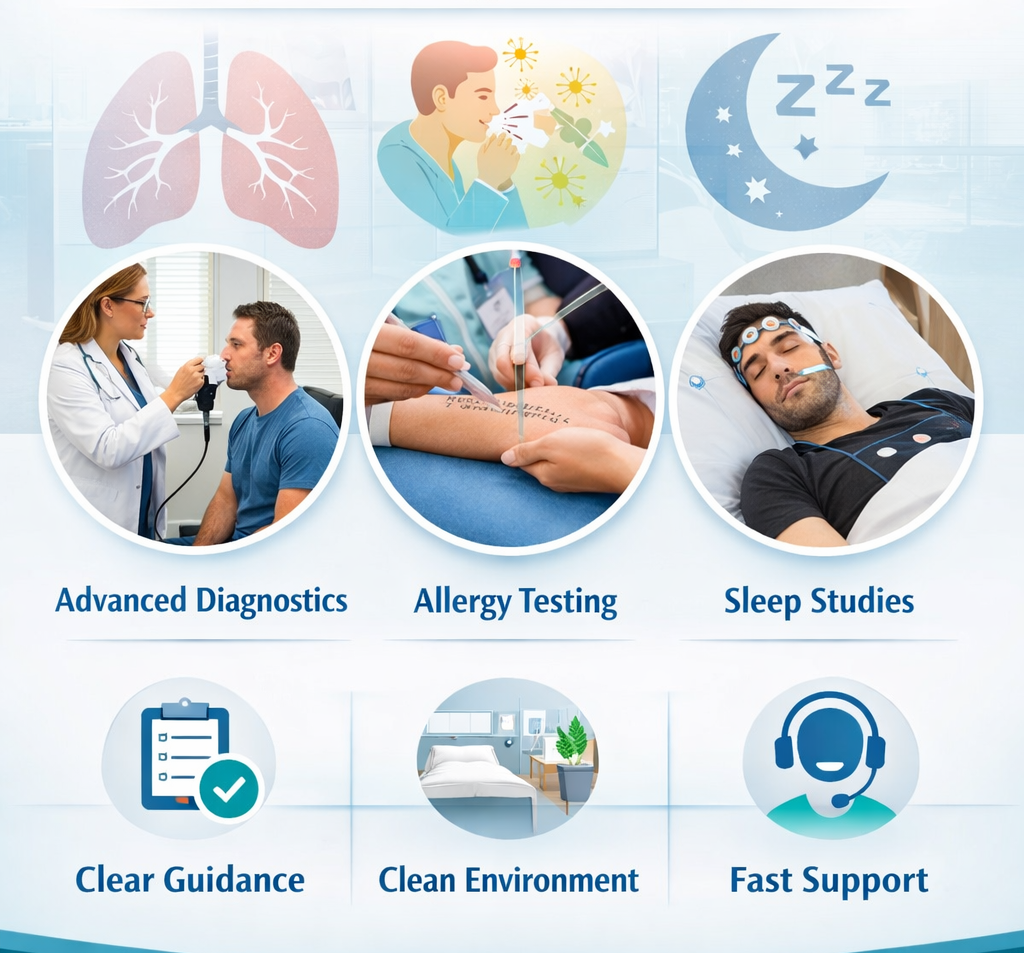

Level -1 Sleep Lab & CPAP Titration

Good Sleep Is Not A Luxury, it's a Necessity

- • Most advanced Sleep Lab of Bhopal

- • Treatment for Snoring, Sleep Apnea, Excessive Sleepiness, Insomnia Etc.

Allergy Testing & Immunotherapy

"Treat The Cause, Not Just Symptoms"

- • Identify & Treat The Root Cause – Not Just Temporary Relief.

- • Aim To Reduce Lifelong Allergy Medicines

Our Services

We provide complete care for chest diseases, allergy treatment, sleep disorders, critical care, and advanced pulmonary procedures with modern facilities and patient-friendly support.

Sleep Medicine

Sleep study & CPAP

PSG, CPAP/BiPAP titration, comfort settings & follow-ups.

Explore → ›

Lung Function Testing

Accurate diagnosis & report.

CPAP / BiPAP

Titration + comfort support.

Allergy Testing

Triggers + prevention plan.